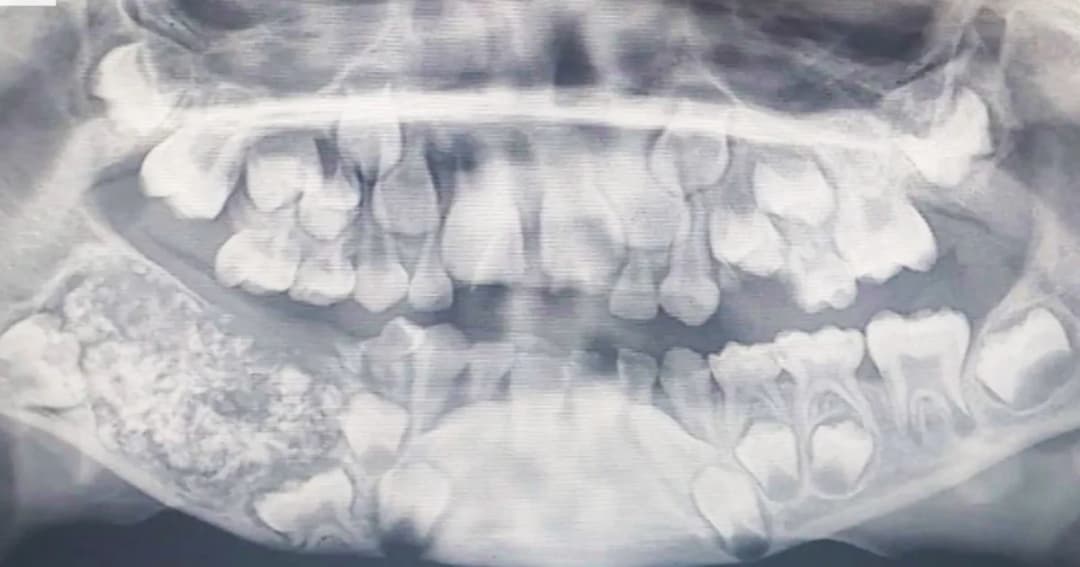

สุขภาพช่องปาก มีราคาที่ต้องจ่าย เมื่อทันตแพทย์ไทย 1 คน ต้องดูแลผู้ป่วยบัตรทองถึง 9,150 คน20 ก.พ. 2568